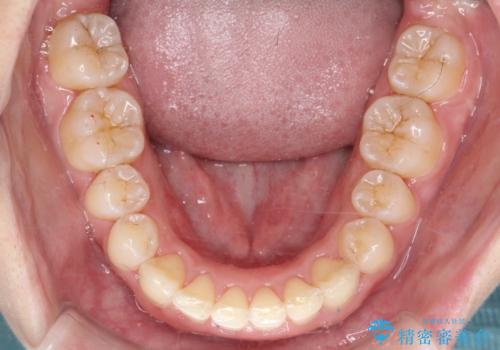

ワイヤー矯正にて下顎前歯の圧下と臼歯部の挺出を効率的に行うことができました。

下顎前歯も綺麗に見えるようになり大変満足していただきました。